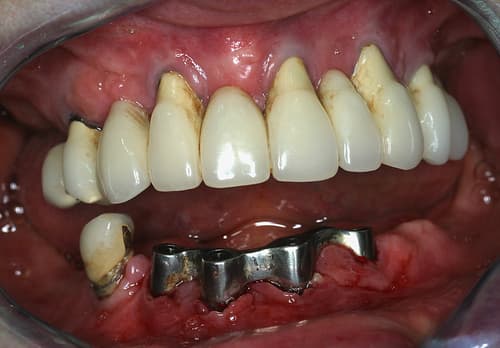

Per-opératoire